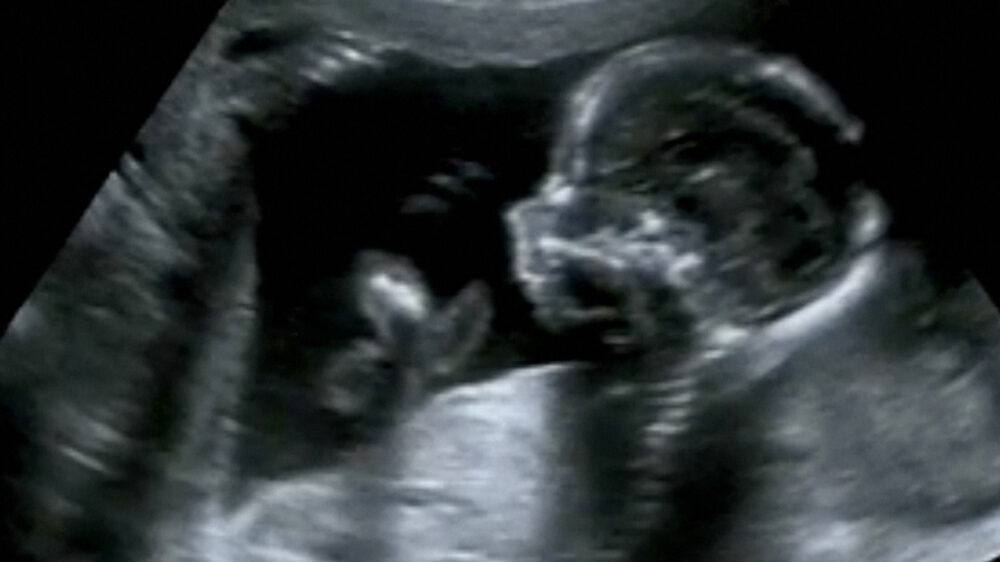

Bisher sind Schwangerschaftsabbrüch laut §218 StGB nur in Ausnahmefällen erlaubt. Die Linke will das ändern.